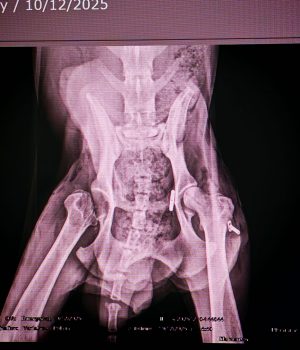

Seine Verletzungen waren schwer: mehrere Brüche der hinteren Gliedmaßen, schlechte Blutwerte und massive Verletzungen im Gesichtsbereich.

Inzwischen hat er zwei schwere Operationen an den hinteren Beinen sowie eine aufwendige Gesichtsrekonstruktion erstaunlich gut überstanden.